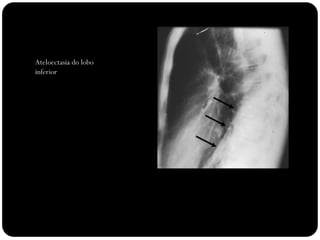

Atelectasia lobo

inferior direito

Observar:

Atelectasias de lobos

inferiores deslocam

o hilo posterior e

medialmente;

Ateloectasia do lobo

inferior esquerdo

Atelectasia do LIE

 Atelectasia LIE:

 Opacidade triangular na área retrocardíaca

em incidência frontal;

 Fissura oblíqua deslocada mais

posteriormente e rodada em orientação

mais sagital do que a orientação coronal

normal;